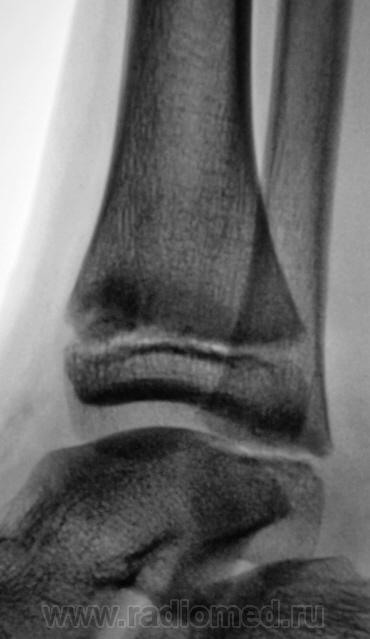

Травма. Пациент направлен на рентгенографию голеностопного сустава.

Травма. Пациент направлен хирургом на рентгенографию голеностопного сустава. Произведено стандартное исследование.

Уважаемый Валентин Львович! А что в жалобах, анамнезе? В переднемедиальной зоне дист. метафиза б/берцовой кости субхондрально под зоной роста участок уплотнения к/структуры, не отграниченный от неизмененной костн. ткани. Возможно, это импрессионный перелом? или остеонекроз? Смущает небольшой очаг аналогичной структуры в таранной кости под медиальным валом блока.

Клиника перелома. Травма - за 4 часа до исследования.

Согласен с коллегой helenmar по поводу перелома по типу импрессии, а ещё подвывих стопы в г/стопном суставе.

У взрослого такие соотношения в суставе назову супинационным подвывихом, хотя прямая проекция не оптимальна для такого заключения, боковая вовсе косая.